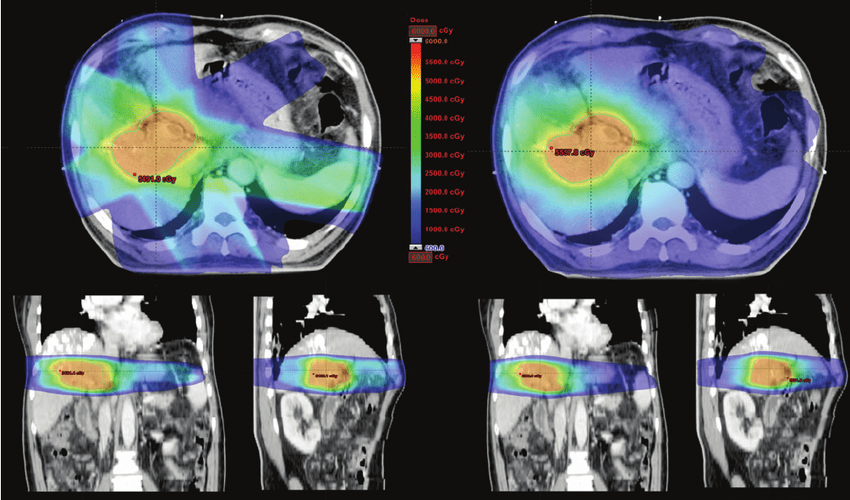

RapidArc delivers highly conformal radiation in a single or multi-arc rotation around the patient using a linear accelerator (LINAC). It adjusts the:

• Beam shape (via multi-leaf collimators)

• Radiation dose rate

• Gantry speed (rotation of the machine)

• Better organ sparing: reduces radiation to nearby healthy tissues